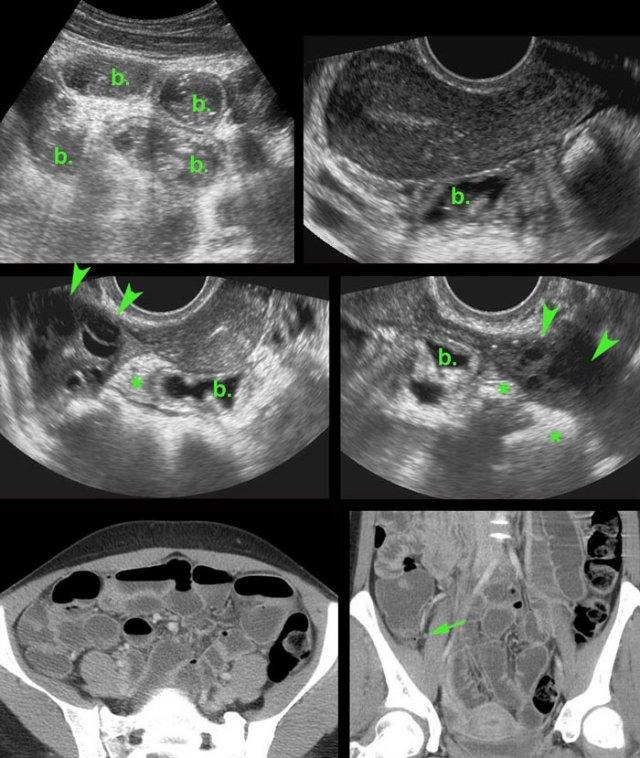

Các hình ảnh này của một phụ nữ trẻ bệnh nặng, đau nhiều với viêm phúc mạc toàn thể và CRP 250, nghi ngờ lâm sàng là thủng ruột thừa.

Siêu âm cho thấy ruột non mất nhu động (b.).

Không quan sát được ruột thừa.

TVUS cho thấy tử cung bình thường và buồng trứng bình thường (đầu mũi tên), được bao quanh bởi mô tăng âm (*).

CT xác nhận hình ảnh liệt ruột và ruột thừa bình thường (mũi tên).

PCR dương tính với lậu cầu.